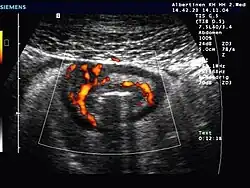

Darüber hinaus muss eine Reihe anderer Krankheiten ausgeschlossen werden, was mit Hilfe von Bildgebung (Sonografie, CT) und zusätzlichen Untersuchungen geschieht: